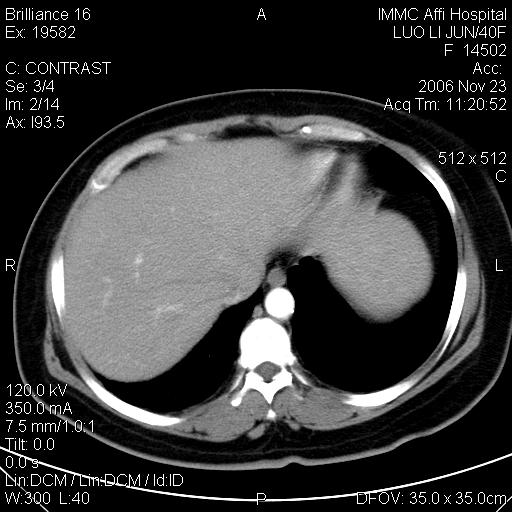

标题: CT5664:我也发一个肝脏的片子大家看看

很典型的肝癌。

典型肝癌

肝癌

速升速降,典型肝癌.

支持-----考虑肝癌----[-从片上看增强早期应该是动脉晚期即门脉早期]

是啊,典型的早出早归!

快进快出典型肝癌.

病灶好圆!可能恶性度不高。

不能除外肝细胞腺瘤吧,还是得结合病史。

很好的片子,可惜增强做的比较失败,a期时间没有把我好,实际到了静脉早期了,否则会更典型。

最终考虑是肝腺瘤